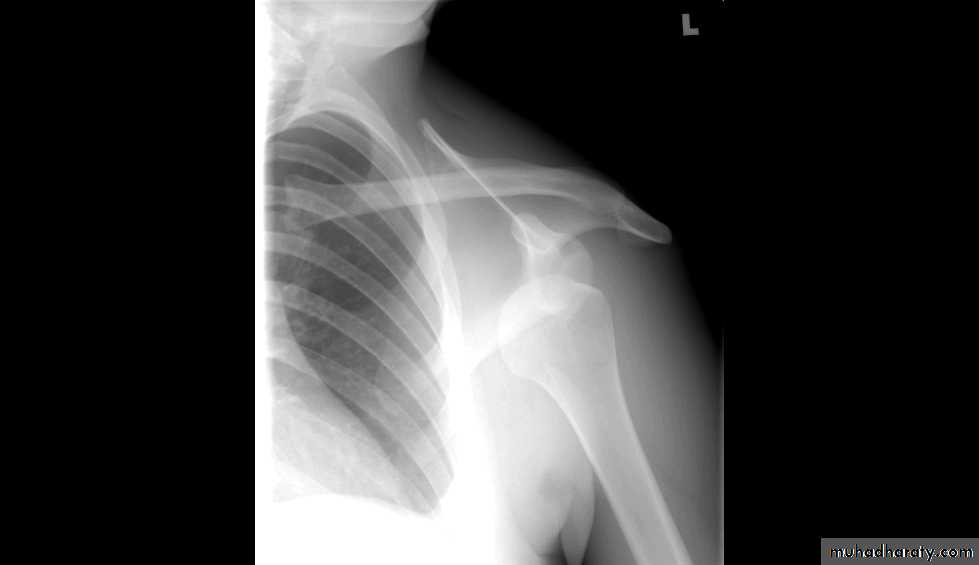

47Shoulder Dislocation/Anterior Instability

Humeral head dislocates from glenoid fossaAlmost always anterior (95%)

Usually traumatic with injury to capsule-labrum complex

X RAYS

DIAGNOSIS???